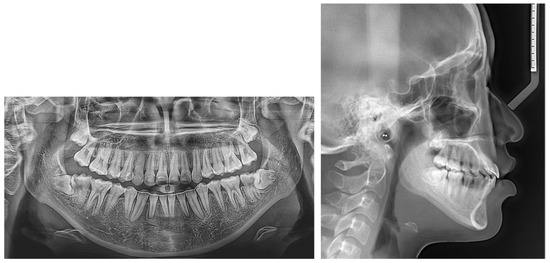

2.5. Treatment Results